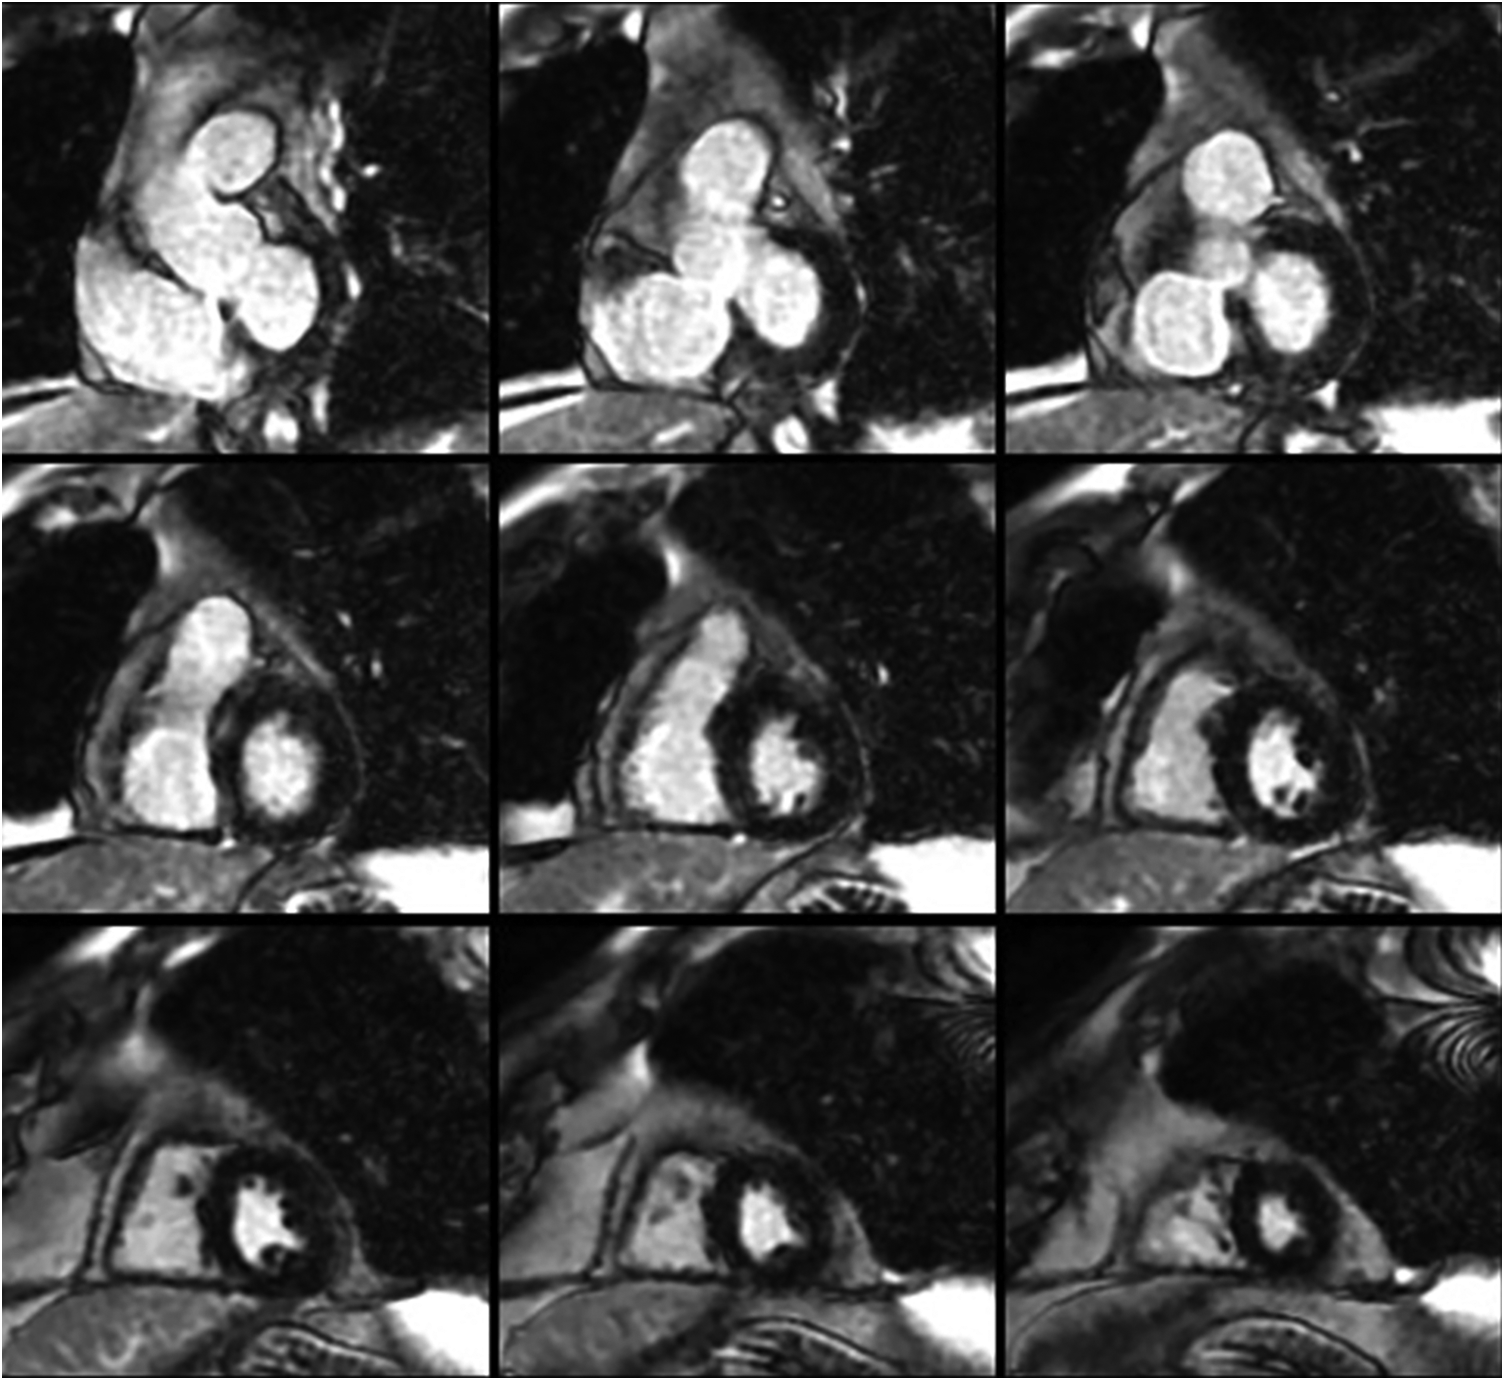

Figure 1

Short-axis cardiac magnetic resonance images demonstrating normal biventricular size and no evidence of late gadolinium enhancement.